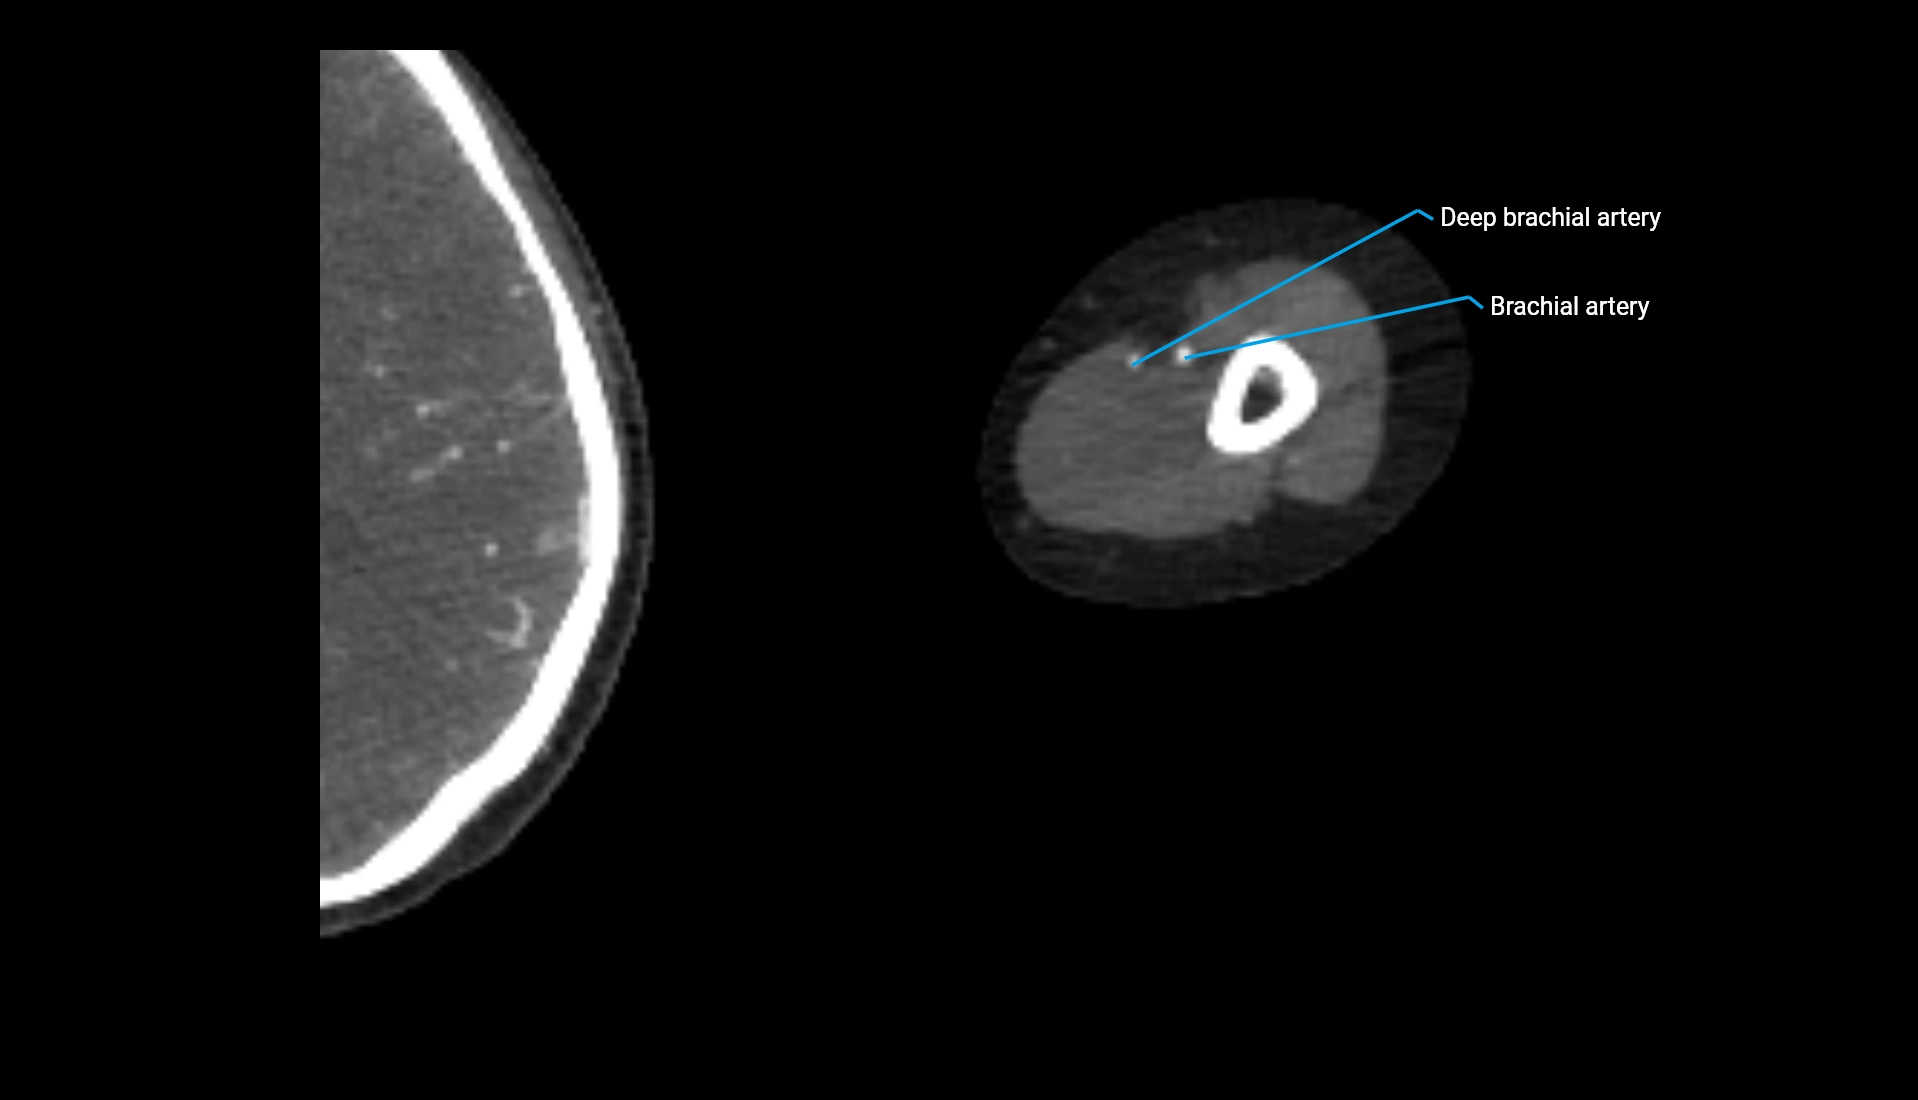

CT Appearance

Non-Contrast CT:

• Cortex: High-density, sharply defined

• Subchondral bone: Dense cancellous matrix

• Articular surface: Smooth concave contour articulating with the capitellum

• Excellent for evaluating bone integrity, alignment, and subtle fractures